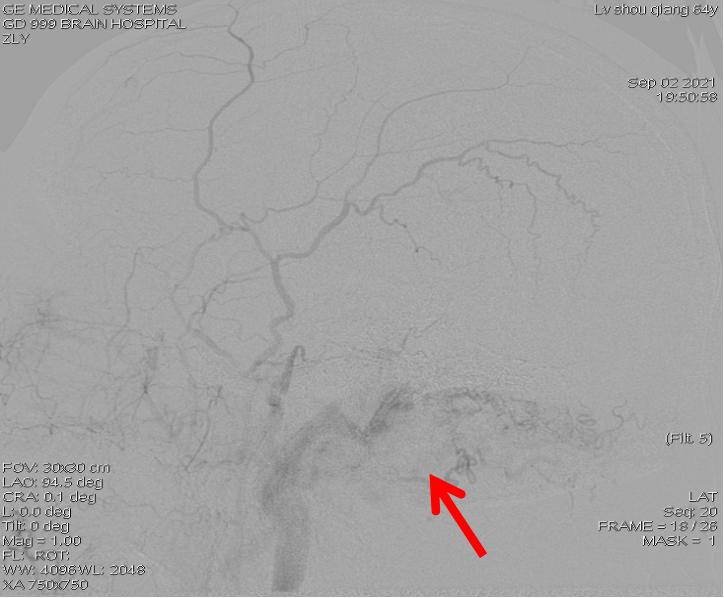

术后影像显示:该支供血瘘口闭塞

由于内科与外科专家共同监测并及时予以手术干预,卢伯的情况明显转好,耳鸣、睡眠不良的情况大大改善。“不用再受耳鸣困扰,终于可以睡个好觉了!”卢伯高兴地说道。